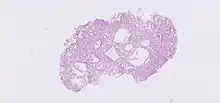

As glândulas gástricas estão localizadas em diferentes regiões do estômago. Estas são as 'glândulas fundicas' ', as' glândulas cardíacas 'e as' 'glândulas pilóricas' . As glândulas e as fossas gástricas estão localizadas na mucosa gástrica. As próprias glândulas estão na lâmina própria da membrana mucosa e se abrem para as bases das fossas gástricas formadas pelo epitélio.[1] As várias células das glândulas secretam muco, pepsinogênio, ácido clorídrico, fator intrínseco, gastrina e bicarbonato.

Os três tipos de glândula estão todos localizados abaixo das fossas gástricas dentro da mucosa gástrica - a membrana mucosa do estômago. A mucosa gástrica está repleta de inúmeras fossas gástricas que abrigam 3-5 glândulas gástricas.[2][3]

As glândulas cardíacas são encontradas na cárdia do estômago, que é a parte mais próxima do coração, fechando a abertura onde o esôfago se une ao estômago. Somente glândulas cardíacas são encontradas aqui e secretam primariamente muco.[4] Eles são menos numerosas que as outras glândulas gástricas e são posicionados mais superficialmente na mucosa. Existem dois tipos - glândulas tubulares simples com ductos curtos ou glândulas racemose compostas que se assemelham às glândulas de Brunner duodenais.

As glândulas fúngicas (ou glândulas oxínticas) são encontradas no fundo e no corpo do estômago. São simples tubos quase retos, dois ou mais dos quais abrem em um único duto. "Oxíntico" significa secreção de ácido e secretam ácido clorídrico (HCl) e fator intrínseco.[4]

As glândulas pilóricas estão localizadas no antro do piloro. Eles secretam gastrina produzida por suas células G.[5]